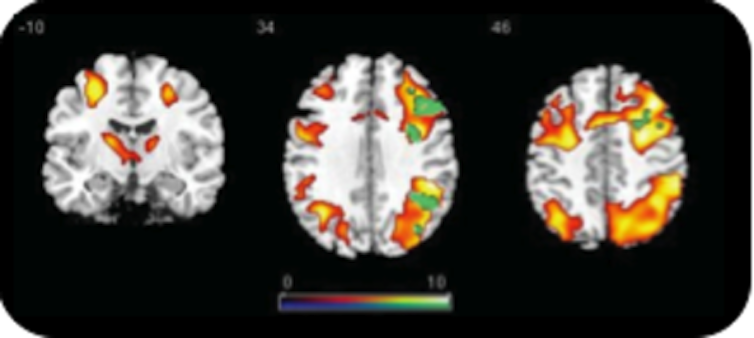

Subtract the patterns from each other, do some more statistics, and the result is a neat coloured blob on a picture of the brain.

Since the only real difference between the playing conditions is your mental state, the difference in brain activity must be specific to that type of mental state.

So the blob signifies the part of the brain that explains why we interact differently with people and computers.

Thousands of papers have subsequently been published, all with images of blobs on brains.

Going from the magnetic pulses to the coloured blobs is fraught with methodological and statistical choices that can completely change what the blobs will look like.

That’s because mental states and brain areas do not have a one-to-one relationship. And all the variability this causes generates scepticism.

But stable patterns of blobs are evident and a lot of the variability seems due to subtle differences in tasks and experimental designs. Nevertheless, there’s still serious discussion about the best method of brain scanning and no doubt many findings from the first 20 years of fMRI will not survive the next 20.